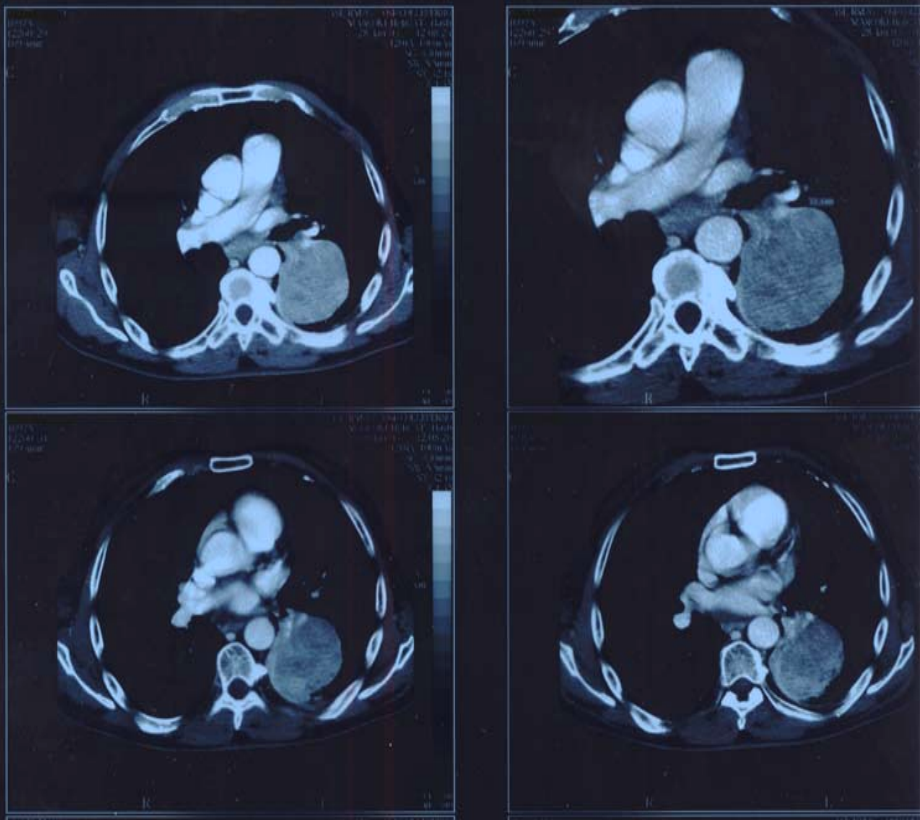

Observations on the report of a case of pulmonary adenocarcinoma with lymph node, hepatic and osseus metastasis.

Figure1